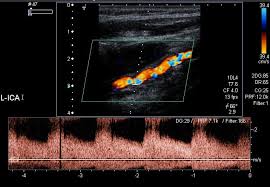

경동맥 초음파 검사는 고주파 초음파를 사용하여 목의 경동맥 혈관을 영상으로 확인하는 검사입니다. 혈관 내벽 두께, 혈류 흐름, 좁아진 정도 등을 실시간으로 볼 수 있으며, 조영제나 방사선 노출이 없어 안전합니다. 검사 시간은 약 20~30분 정도 소요됩니다.

경동맥의 협착 정도와 혈류 속도를 확인해 향후 뇌졸중 발생 가능성을 예측할 수 있습니다.

혈관 내막 두께, 협착 정도, 혈류 속도 등을 확인할 수 있으며, 결과에 따라 추가 정밀검사가 필요할 수 있습니다.